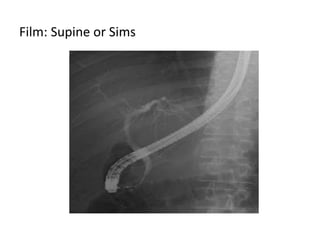

Contrast material (dye) is then injected and X-rays

are taken of the bile ducts and the pancreatic duct.

Film: Supine or Sims